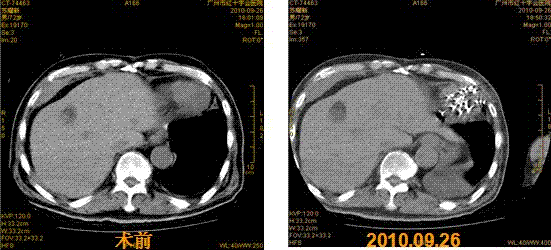

碘-125放射性粒子植入即刻,3月后复查肿块大部萎缩,9月时复查心包内肿块完全萎缩。